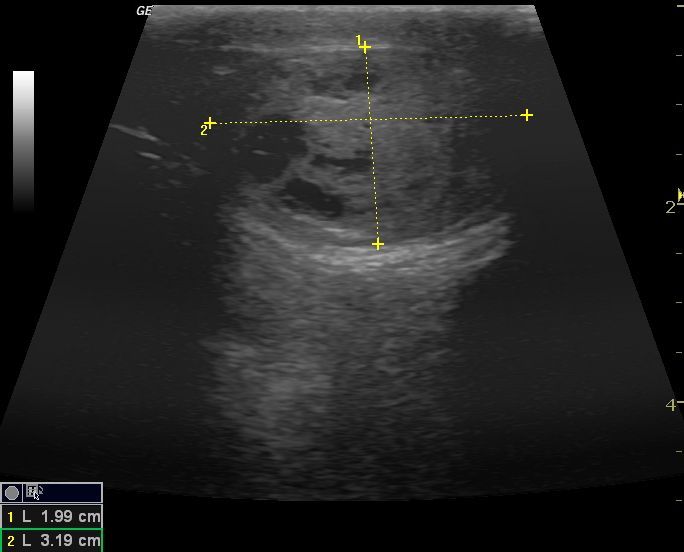

La ecografía como diagnótico de gestación es a día de hoy el método más fiable durante el primer trimestre, además nos aporta datos para predecir la fecha de parto, y realizar un seguimiento del desarrollo de los fetos, pudiendo evaluar el estres fetal.